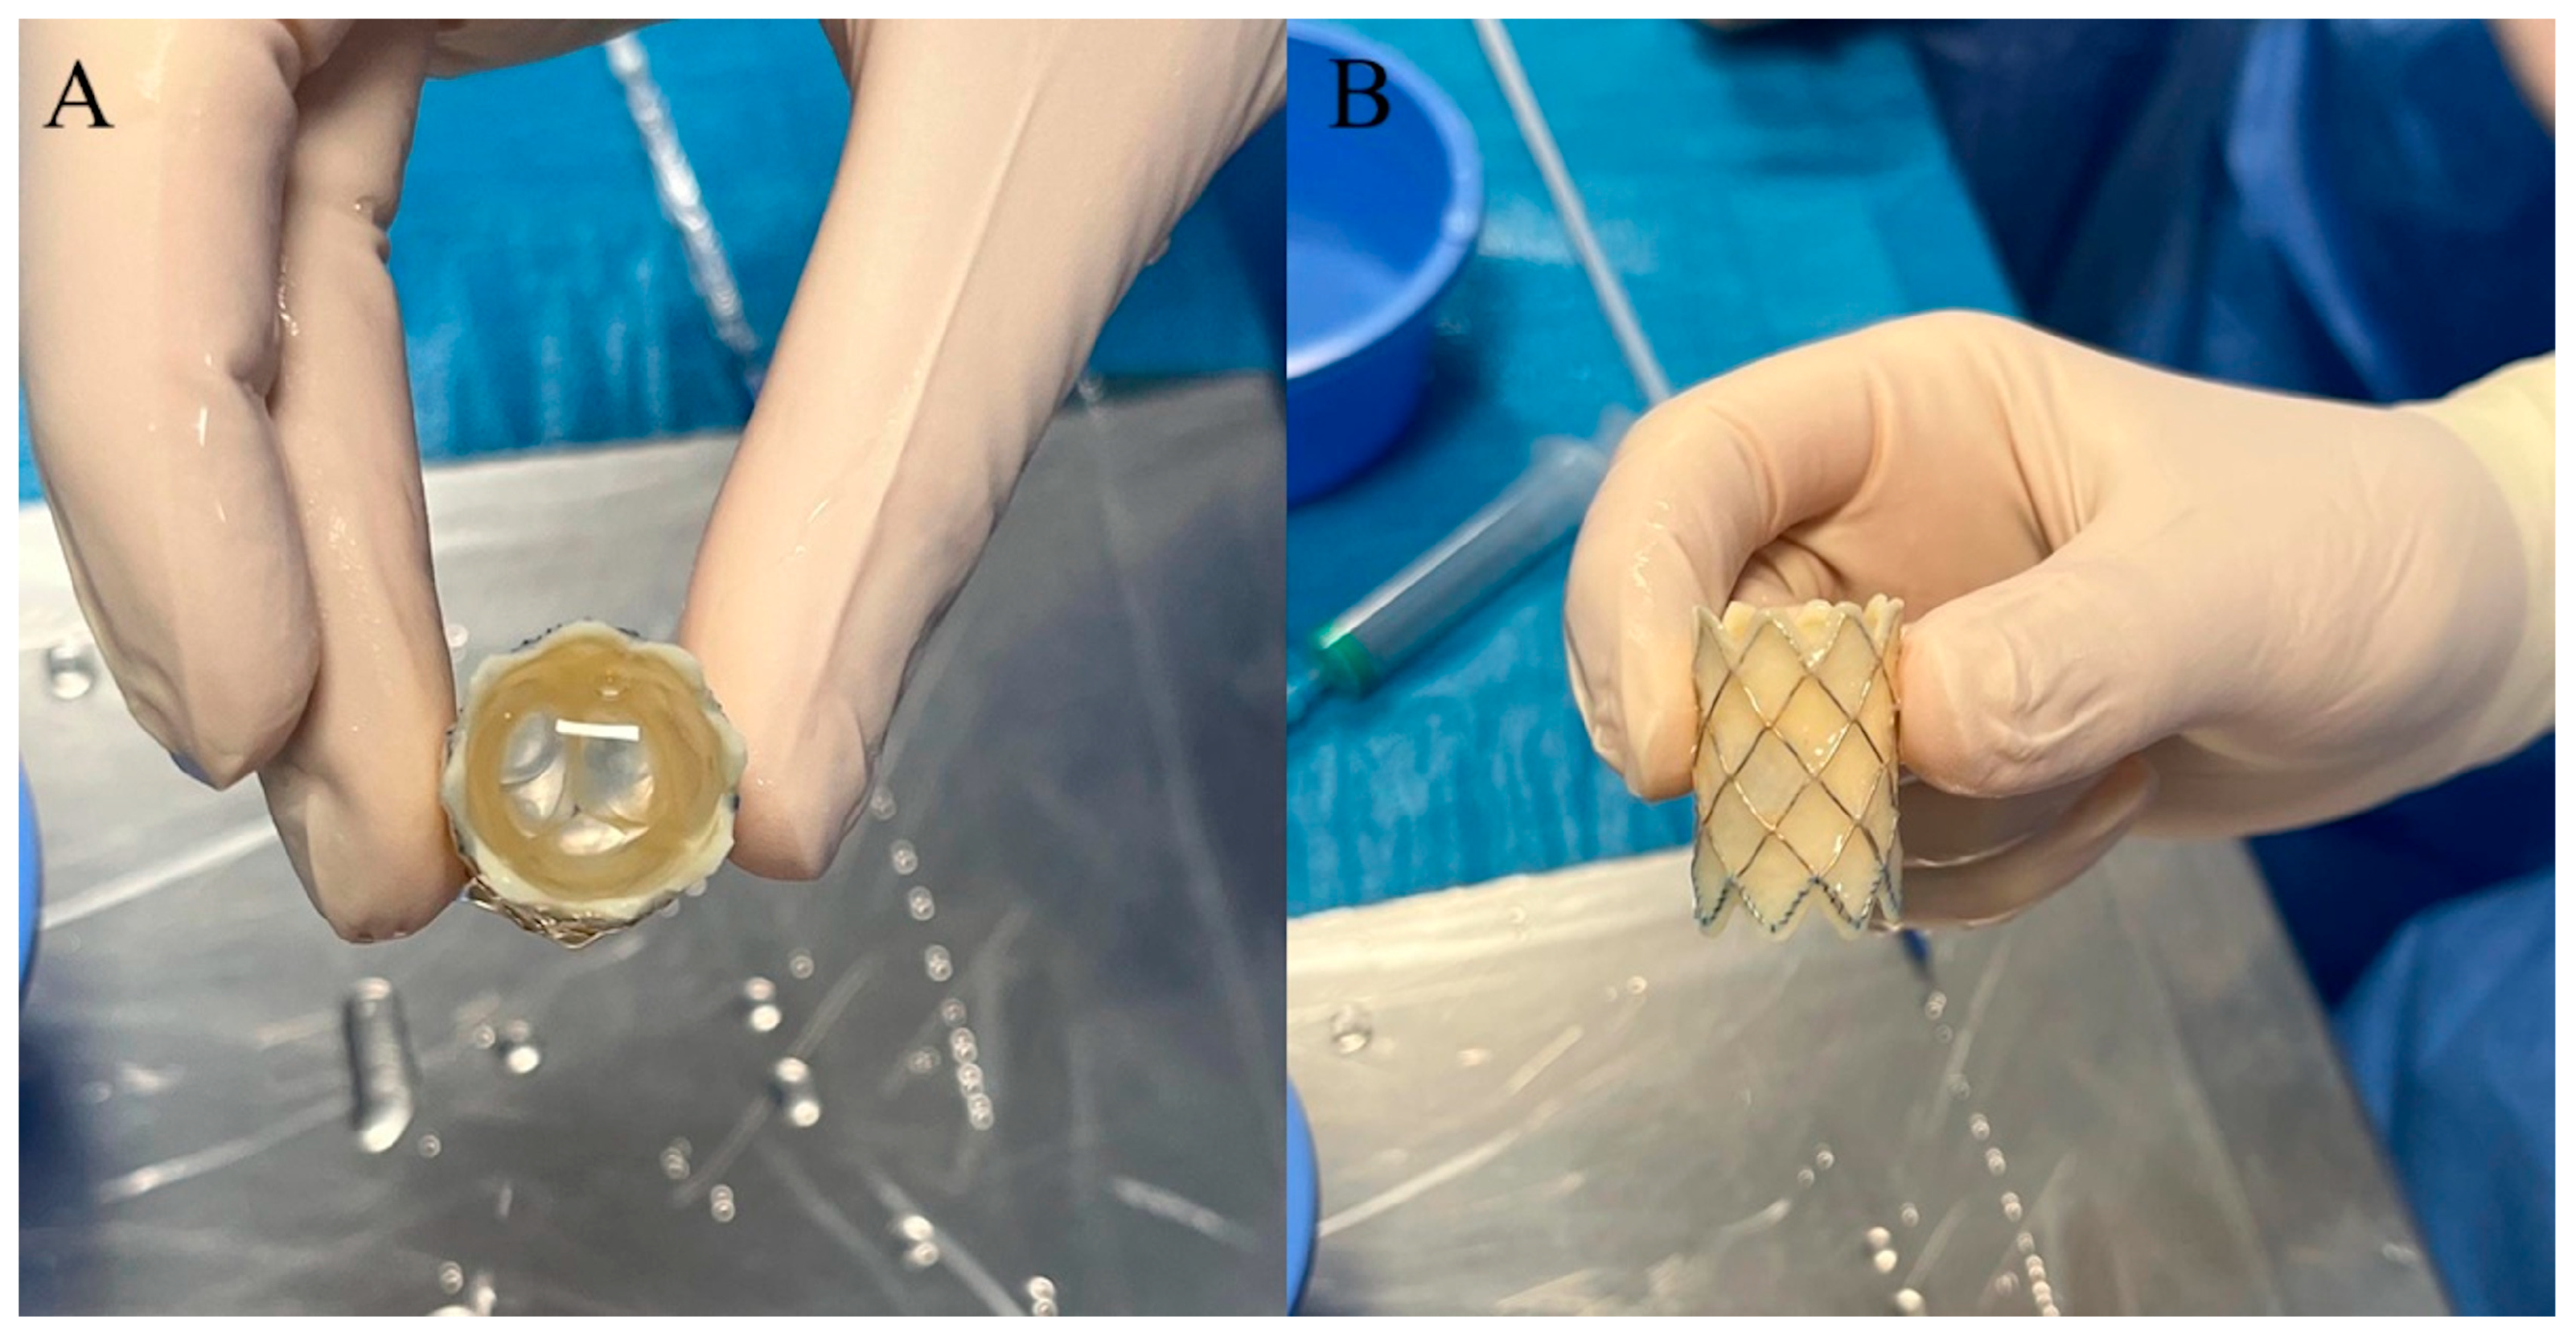

3. Melody Transcatheter Pulmonary Valve

- Boe, B.A.; Cheatham, S.L.; Armstrong, A.K.; Berman, D.P.; Chisolm, J.L.; Cheatham, J.P. Leaflet morphology classification of the Melody Transcatheter Pulmonary Valve. Congenit. Heart Dis. 2019, 14, 297–304. [Google Scholar] [CrossRef] [PubMed]